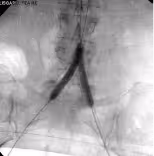

Many peripheral stenoses and occlusions are accessible by endovascular means. Among the endovascular procedures treatment of iliac and femoro-popliteal stenoses/occlusions are the most often used techniques. Thorough planing, proper use of endovascular tools and adherence to meticulous endovascular techniques are therefore of upmost importance for the success.